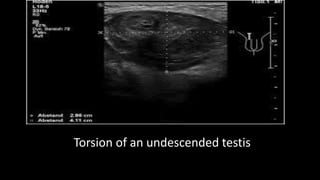

This document discusses the evaluation of right lower abdominal pain and lists appendicitis as a key cause. It notes that other potential causes include hemorrhagic cysts, heterotrophic pregnancy, salpingitis with pyosalpinx, funiculitis, and torsion of an undescended testis. The document was presented by Dr. A.S.M. Sufian of Cumilla Medical College Hospital and thanks the audience for their patience and listening.